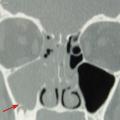

Dans les sinusites maxillaires où l’origine dentaire est suspectée, il est également nécessaire de prescrire un scanner du massif facial (fig. 3) [souvent complété par un dentascanner, un panoramique dentaire et/ou des clichés rétroalvéolaires] et de faire pratiquer un bilan odontologique.